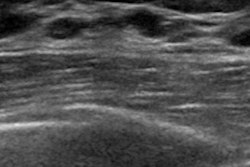

Imperial College London researchers are combining ultrasound with supercomputing to detect breast cancer in a new project, Quantitative Ultrasound Stochastic Tomography (QUSTom).

To obtain the images, researchers will develop mathematical algorithms that can show the image of the patient's tissue and its associated uncertainty, pixel by pixel. It also incorporates multimodal imaging and 3D imaging, which is an unprecedented combination in ultrasound breast imaging.

The technology, which uses no radiation, is expected to offer superior image quality, better monitoring of tumors, and other benefits. The researchers hope the imaging will complement or replace current techniques, such as mammograms.